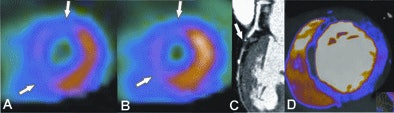

![]() |

| Fifty-eight-year-old woman with recurring chest pain. Extensive, fixed perfusion defect is observed at stress (A) and rest (B) SPECT myocardial perfusion imaging. Contrast-enhanced retrospective electrocardiogram-gated DECT study: Coronary CTA reconstruction displayed as curved multiplanar reformat (C) shows total thrombotic occlusion of the distal left anterior descending artery to the first diagonal branch (arrow). Short-axis view (C) shows corresponding anteroseptal contrast defect (arrows) in good correlation with fixed perfusion defect at SPECT. |